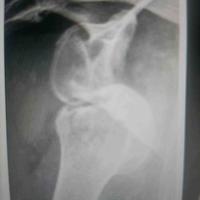

肩关节前脱位伴明显的Hill Sachs

肩关节前脱位伴明显的Hill Sachs....